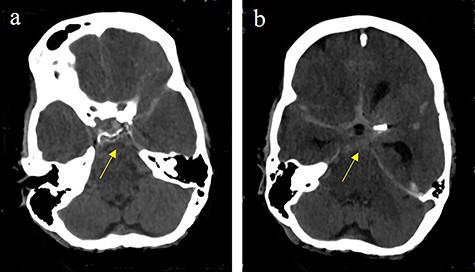

Massive progress of SAH axial cCT at the level of (a) prepontine cistern (arrow) and (b) pentagonal cistern (arrow)

On the next day (Day 9 post-op), the patient suffered from acute and devastating headaches, with screaming and enuresis. An emergency computed tomography (CT) was carried out and displayed a prepontine and retroclival subarachnoid hemorrhage (Hunt & Hess Grade I), (Fig. 2). For further evaluation, a digital subtraction angiography (DSA) was conducted, and it showed a pseudoaneurysm of ophthalmic1/supraclinoid2/C23 part of the left ICA, which was directly treated by a flow diverter (Derivo®—4,5/20), with remaining rest flow (Fig. 3). The patient was transferred to the ICU, transcranial doppler sonography was performed and revealed normal flow. In the following course, the patient suffered from Terson’s syndrome and hyponatremia due to SIADH, but after clinical improvement, was transferred back to normal station after 10 days of post-operative monitoring. Furthermore, the patient was plagued with cephalgia and nausea, which could not be compensated with analgetics and antiemetics. On the 20th post-operative day after the epileptic seizure with postictal vigilance reduction, an emergency CTA was conducted showing progressive SAH (Fig. 4) and a growing pseudoaneurysm as well as generalized vasospasm with posthemorrhagic hydrocephalus. For an emergency CSF diversion, an external ventricle drain was placed. The repeated DSA showed a growing false aneurysm which was treated with two additional flow diverters (2× Derivo®—4,5/20) as well as coiling (HydroSoft™ 2/3 and 2× 1,5/2) by endoleak (Fig. 5). The vasospasms were treated by an intraarterial spasmolysis (Fig. 6).